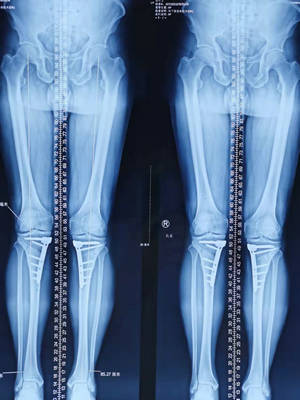

第二天,邱東新醫生為患者進行了關節鏡下探查清理+機器人輔助下的脛骨截骨術。術中,取左膝關節臏韌旁內外側各做0.5cm左右切口,透過關節鏡探查發現內外側半月板複雜撕裂,內側股骨髁、脛骨平臺軟骨三度磨損,髁間窩骨贅明顯,但慶幸的是前交叉韌帶、外側軟骨狀態良好,予內側半月板成型,清理出部分磨損的軟骨和髁間窩骨贅。然後在左脛骨中段內側打入導航定位螺釘進行精準截骨,很大程度的減少了對周圍組織的損傷,術中出血量少,創傷小,恢復也就更快。

手術很成功,術後當天,折磨張師傅許久的疼痛就消失了,術後第二天,就可以下床行走,左腿也不一瘸一拐了,張師傅十分滿意,過了一段時間,張師傅找邱醫又做了右膝關節的保膝手術。